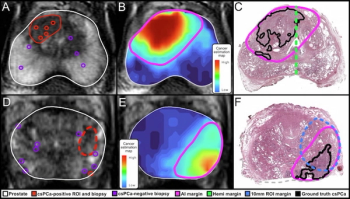

Combining multimodal imaging data and biopsy data, an artificial intelligence (AI) model provided enhanced sensitivity for defining prostate cancer tumor margins in comparison to conventional magnetic resonance imaging (MRI) assessments.